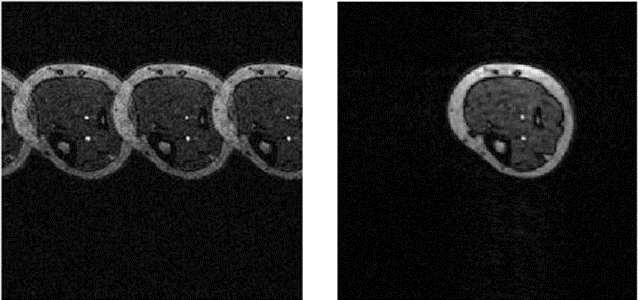

并行成像(Grappa):GRAPPA算法是一种利用所有通道的中心完整采样的数据,计算一个通道 K 空间内某点及其特定邻近位置的多个点(包括所有通道在这些特定位置的对应点)的权重,再利用已采集的数据和权重去重建这一通道的未采集的数据点,以此获得完整k空间数据的快速成像方法。

并行成像(SENSE):SENSE技术首先利用不同位置的接收线圈单元计算出各线圈敏感性差异的K空间填充数据,然后由此重建出相应的具有卷褶效应的图像,最后再将这些具有不同线圈敏感性差异的卷褶图像组合成一幅不具卷褶伪影图像。